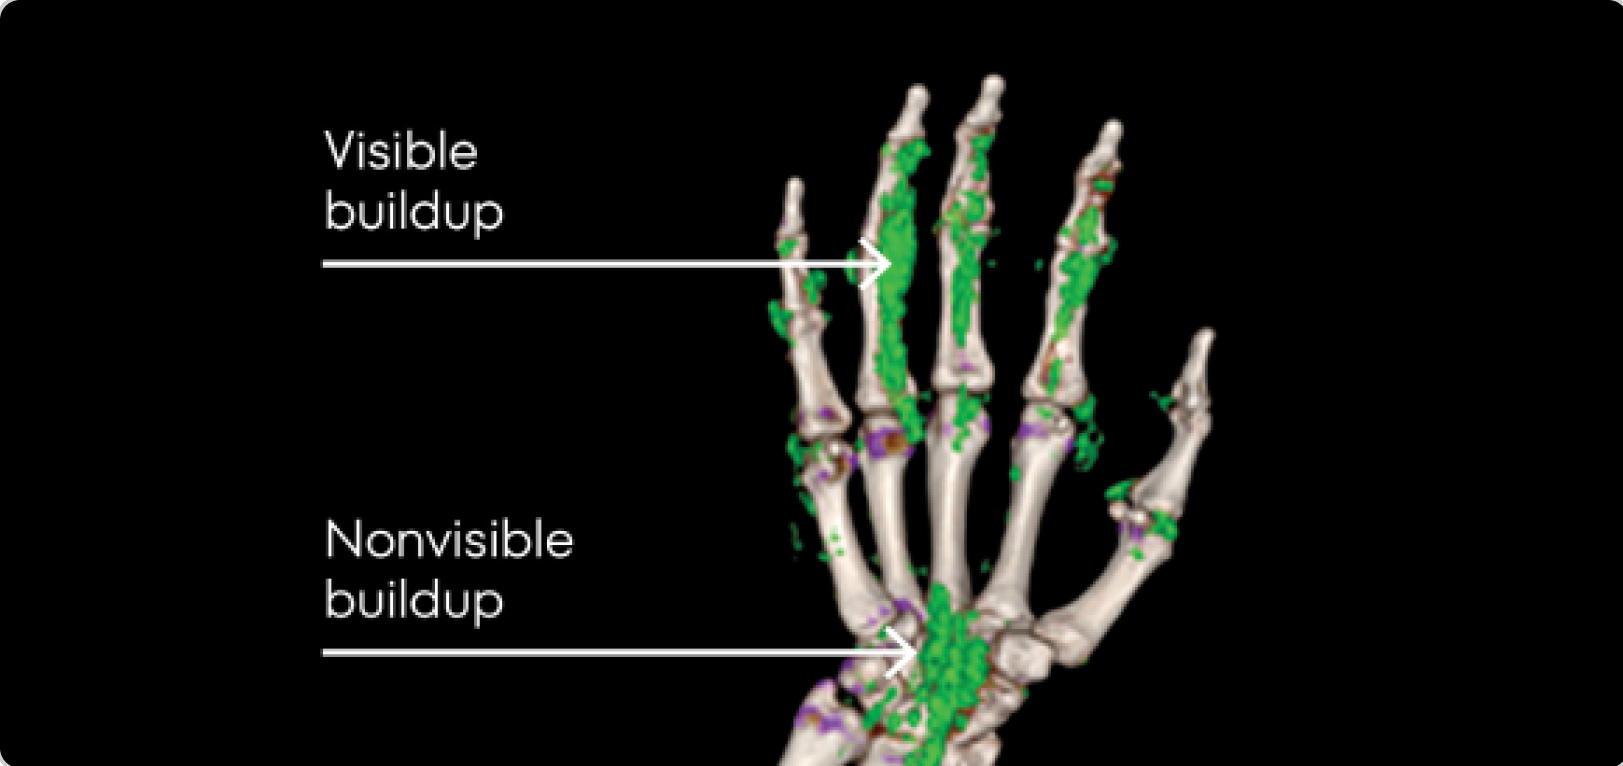

Image of tophi in hands with both visible and nonvisible buildup

PHOTO OF TOPHI BUILDUP

Image courtesy of Dr Jürgen Rech.

KRYSTEXXA is not indicated for the treatment of pain.

Dual Energy CT scan of hand showing visible and nonvisible buildup in gout patient

DECT OF URATE BUILDUP

DECT image courtesy of Dr Jürgen Rech. Green areas indicate urate crystal buildup.

DECT, dual-energy computed tomography.